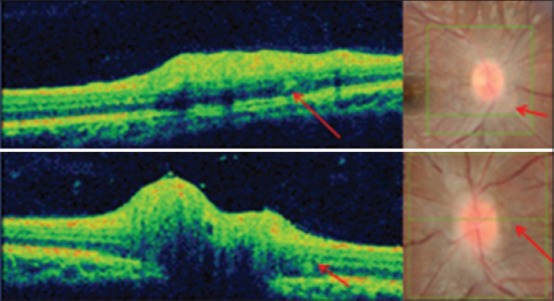

Retinal nerve fiber layer thickness

Table 2 gives the RNFL thickness values in papilledema, pseudopapilledema, and controls. In papilledema, the RNFL thickness was maximum in the inferior quadrant and least in the temporal quadrant. In pseudopapilledema, it was maximum in the superior quadrant and least in the temporal quadrant, but logically in this group, it is based on the location and depth of drusen and can vary from case to case. Comparison of RNFL thickness between the three groups using Kruskal–Wallis test showed a statistical significant difference between the groups (P < 0.001) with RNFL being the thickest in all four quadrants in papilledema than other two groups. Post-hoc Mann–Whitney test with the conservative P value of 0.016 showed a statistical significant difference in RNFL thickness between the groups (P < 0.001) except temporal RNFL which showed no statistical significant difference between papilledema and pseudopapilledema (P = 0.066).

Table 2.

Peripapillary RNFL thickness for all four quadrants, average RNFL thickness and TRT at inferior and superior edge of the optic disc in the three groups; papilledema, pseudopapilledema, and controls

Peripapillary total retinal thickness

Table 2 gives the mean TRT at inferior and superior edge of the optic disc. The mean inferior and superior TRT was increased in papilledema than pseudopapilledema, but the difference was not statistically significant (P > 0.016, post-hoc Bonferroni test). The difference in the mean TRT between Groups 1 and 3 and also Groups 2 and 3 was statistically significant (P < 0.001).